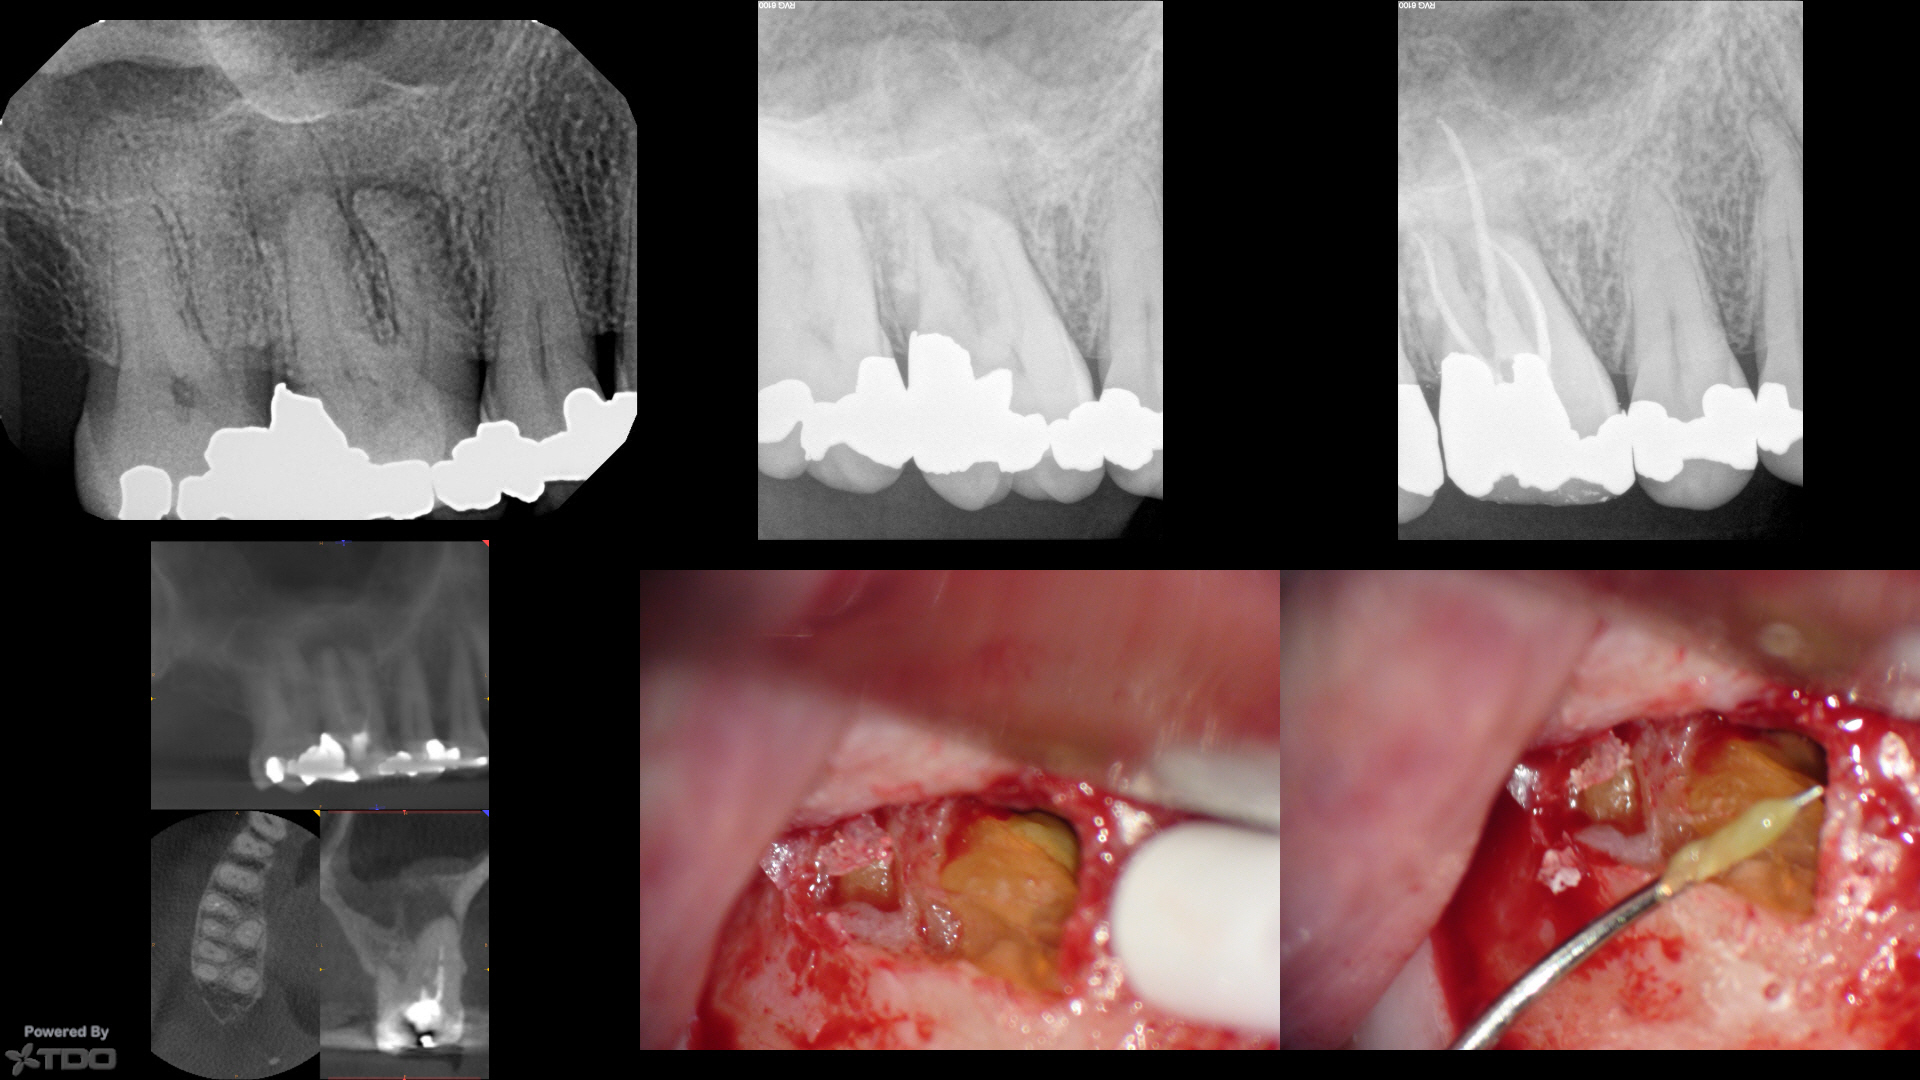

I saw this nice lady last summer Nec/CAP #3 (primarily screening finding prior to crown–very lightly symptomatic), as well as a symptomatic #14 (not shown) post recent filling (the pulp had just died on.#14). We did multi-visit endo on both teeth with #3 becoming completely comfortable right away, and #14 taking some time to settle down. We obturated #3 in September.

A crown was placed on #14 (not shown) and that tooth has remained asymptomatic. Tooth #3 had a temp crown placed in March, had it removed to place the perm crown but the tooth became sore again. She finally came to see me beginning of July with increased findings at CBCT around the MB and DB roots. I had four canals on #3 and didn't feel that retreatment would bring anything to the table, so we scheduled periapical surgery on the buccal roots (the P root had radiographic evidence of osseous regeneration.)

We reflected a flap to discover the green gnar. Most of these cases that are refractory that I re-enter surgically have some sort of root-end gnar. Green gnar, yellow gnar and sometimes orange gnar with sparkles.

Here, I just resected the MB/DB roots to what appeared to be clean bone, curetted out the crypt, placed a Collaplug (to help form a clot…I don't know if it matters). I did not retroprep or retrofill.

If one is very careful doing periapical surgery and sneaks up on the root end with magnification, most of these refractory cases have some sort of accretion/gnar around the root ends.